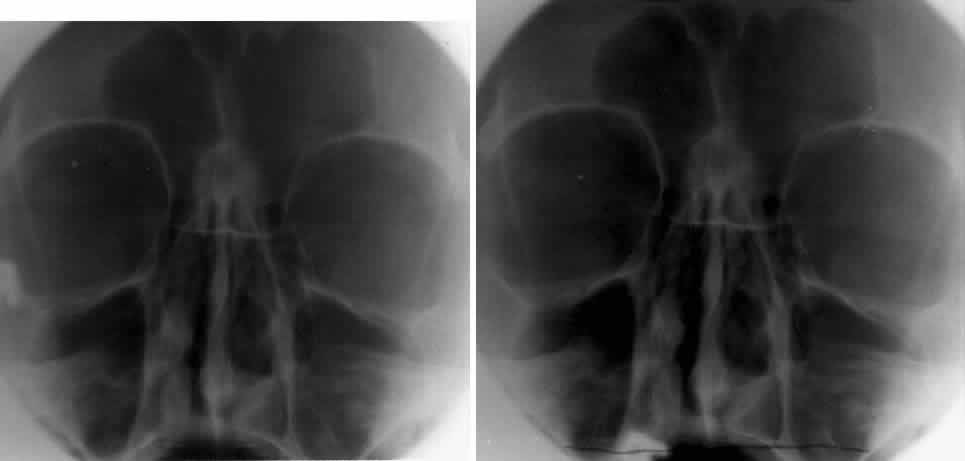

LATERAL PROJECTION

Lateral projection (Fig. 4) is created by placing the patient's head against the x-ray cassette and centering the cassette on the lateral canthus. The x-ray beam is directed perpendicularly to the midpoint of the cassette and enters the patient's head at the lateral canthus remote from the cassette.5,6 This projection provides a view of the sagittal plane of the skull. Because of the overlapping skeletal structures, interpretation of unilateral disease processes is difficult. The structures that can be identified and best evaluated include the sphenoid, frontal, ethmoid, and maxillary sinuses. This lateral view also shows the sella turcica, the anterior and posterior clinoid processes, the nasopharynx, and the cribriform plate. The orbital structure best evaluated is the orbital roof. The floor of the orbit is visible but evaluation is difficult because of the upward slope, from lateral to medial, toward the orbital apex. This slope causes the floor to appear at different levels on the lateral view.11 The lateral projection, although not as useful as the frontal projections, gives information concerning air-fluid levels in traumatized patients, when only a horizontal projection is possible.

Fig. 4. A. Schematic showing positioning for a lateral projection. (CR, central ray) B. Radiograph of a lateral projection. (a, orbital roof; b, frontal sinus; c, ethmoid sinus; d, anterior clinoid process; e, sella turcica; f, planum sphenoidale) (A; Rao VM, Gonzalez CF: Plain film radiography and polytomography of the orbit. In Gonzalez CF, Becker MH, Flanagan JC [eds]: Diagnostic Imaging in Ophthalmology, pp 1–7. New York, Springer Verlag, 1986)